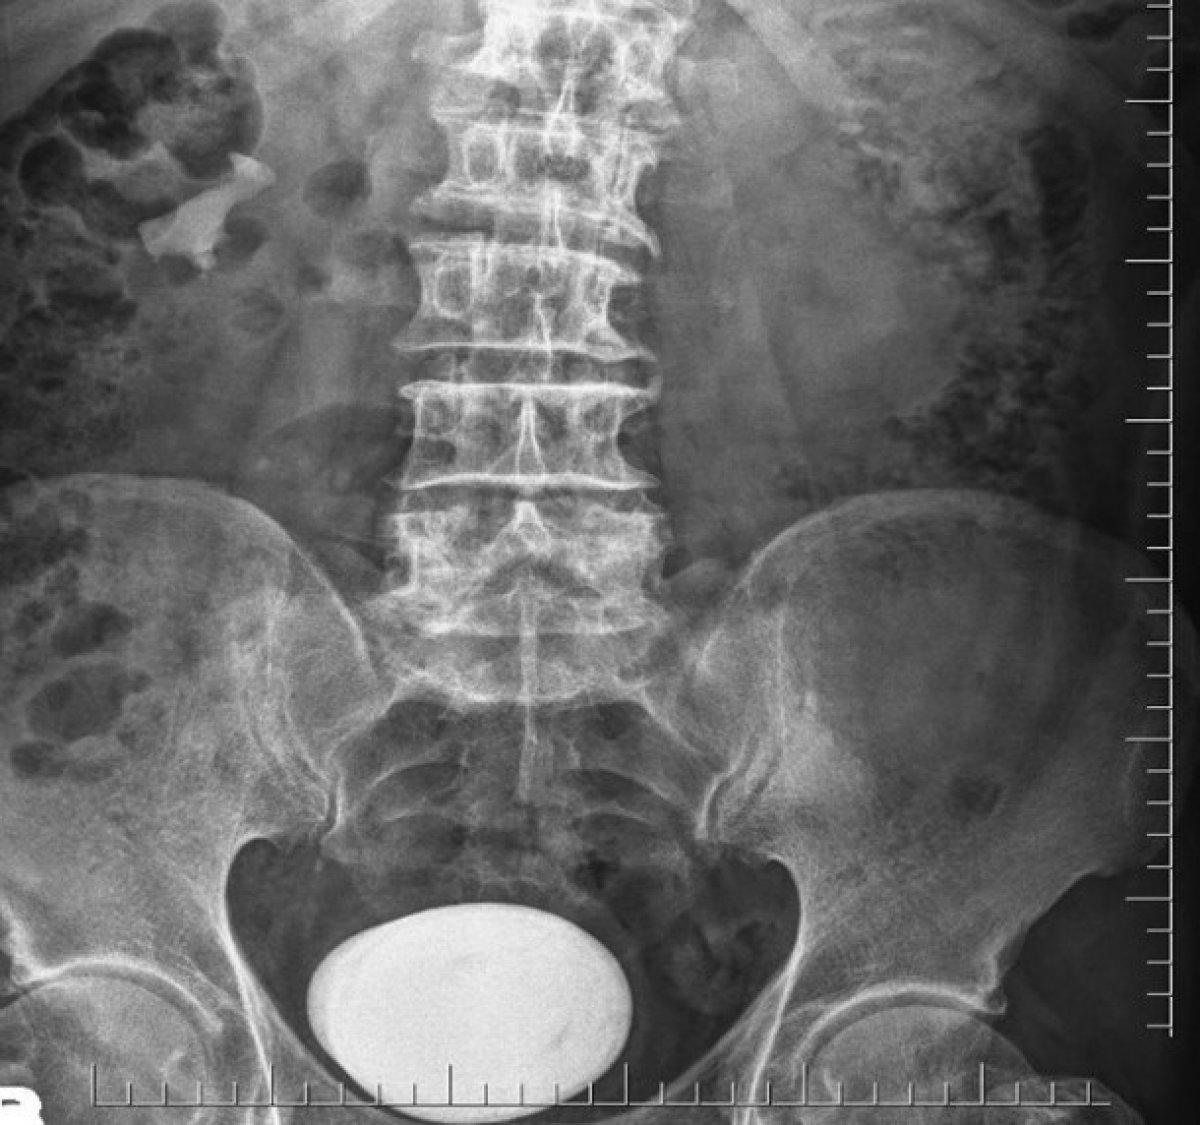

Yapılan tetkik ve tahliller sonucunda hastanın mesanesinde çok büyük bir taş saptandı. Literatürde bu boyda taş görülmesi çok nadir karşılanırken hastanın mesanesinden çıkan taş şaşkınlıkla karşılandı.

Derhal ameliyata alınan hastanın mesanesindeki taş kapalı yöntemle çıkarılması mümkün olmadığından açık sistolitotomi ameliyatı yapıldı.

Herkesi şaşkına çeviren büyük bir patates yumrusu şeklindeki taş başarılı şekilde alındı.